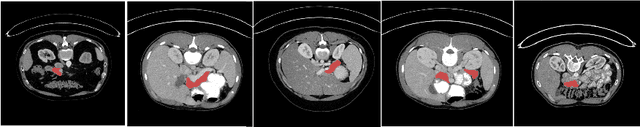

Abstract:Due to the fact that pancreas is an abdominal organ with very large variations in shape and size, automatic and accurate pancreas segmentation can be challenging for medical image analysis. In this work, we proposed a fully automated two stage framework for pancreas segmentation based on convolutional neural networks (CNN). In the first stage, a U-Net is trained for the down-sampled 3D volume segmentation. Then a candidate region covering the pancreas is extracted from the estimated labels. Motivated by the superior performance reported by renowned region based CNN, in the second stage, another 3D U-Net is trained on the candidate region generated in the first stage. We evaluated the performance of the proposed method on the NIH computed tomography (CT) dataset, and verified its superiority over other state-of-the-art 2D and 3D approaches for pancreas segmentation in terms of dice-sorensen coefficient (DSC) accuracy in testing. The mean DSC of the proposed method is 85.99%.